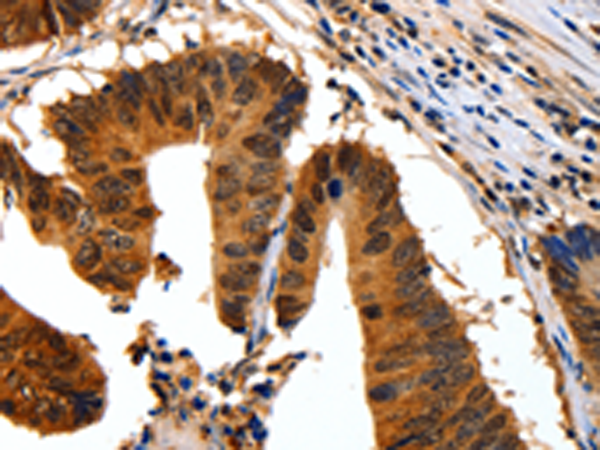

分类: 科研抗体货号: P11032别名: no me应用: IHC反应种属: Human, Mouse